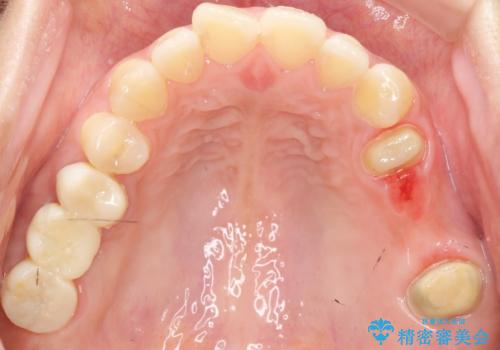

奥歯3本(左上567)はう蝕が深く保存不可能な状態であったため、やむなく抜歯しました。

インプラントも入れ歯も抵抗があるとのご相談により、自家歯牙移植を提案しました。

使っていない親知らず(左上8)を左上7抜歯窩に移植し、支台歯としてブリッジによる補綴治療を行いました。

上顎骨がかなり薄くインプラント治療に対し望ましい状態でないことからも、自家歯牙移植は有意義であったと考えます。